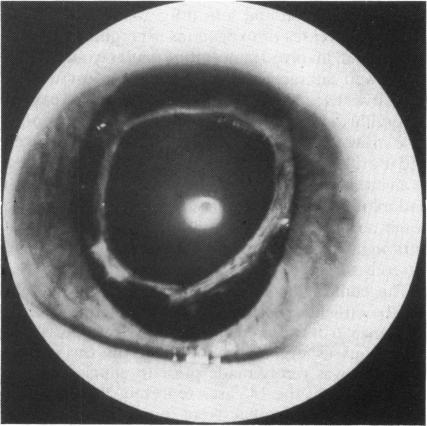

We describe the first case of successfully treated exogenous aspergillus endophthalmitis following penetrating injury and primary scleral wound repair. After repeated vitreous surgery with multiple intravitreous instillations of amphotericin B combined with intravenous antifungal therapy the patient's visual acuity was 6/18. A vigorous approach in the management of mycotic endophthalmitis is emphasised and the role of closed vitrectomy discussed.

我们描述了穿透伤和原发性巩膜伤口修复后成功治疗的首例外源性曲霉性眼内炎病例。在多次玻璃体手术并多次玻璃体内注射两性霉素B联合静脉抗真菌治疗后,患者视力为6/18。强调了在真菌性眼内炎治疗中采取积极措施,并讨论了闭合式玻璃体切除术的作用。